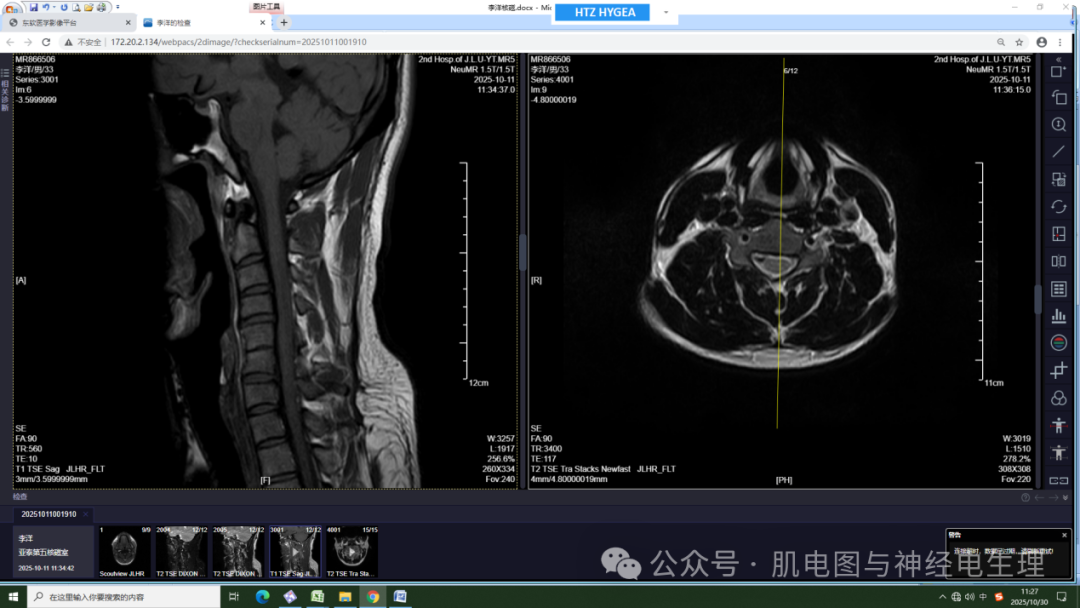

外院腰椎核磁:腰椎曲度存在,各椎体边缘变尖。胸11、腰5椎体边缘局限性凹陷,腰4、5椎体邻近缘见条片状稍长T1稍短T2信号,压脂像呈稍高信号。腰4-5、腰5骶1椎间隙变窄。腰4-5、腰5、骶1间盘信号减低,并向后方突出,以腰5骶1间盘向左后方突出为著。椎管及脊髓内未见异常信号。